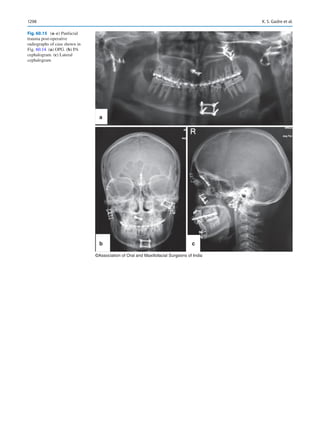

icine man for their healthcare. Direct to consumer marketing